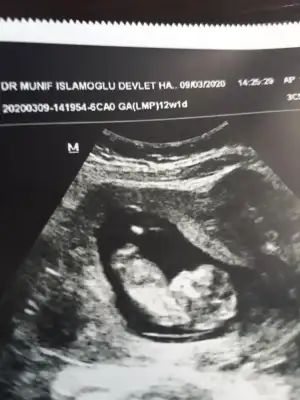

Erkek gibiTahmin edebilcek olan var mı lütfen dr söyledi 12. Haftada bakalım aynı mı

Kız sanki emin olamadım başka usgde paylaşınKızlar tahminde bulunabilirmisiniz ikiz bebekler 12 hafta 1 gunlikler

Bu kadar usg görüntüleri var malesefKız sanki emin olamadım başka usgde paylaşınsagdaki kız gibi digeri hiç görünmüyor

Tek yumurta ikizimi sanki ikiside kız tekrar usg olursa paylaşırsınız 13 haftada olurBu kadar usg görüntüleri var malesef![]()